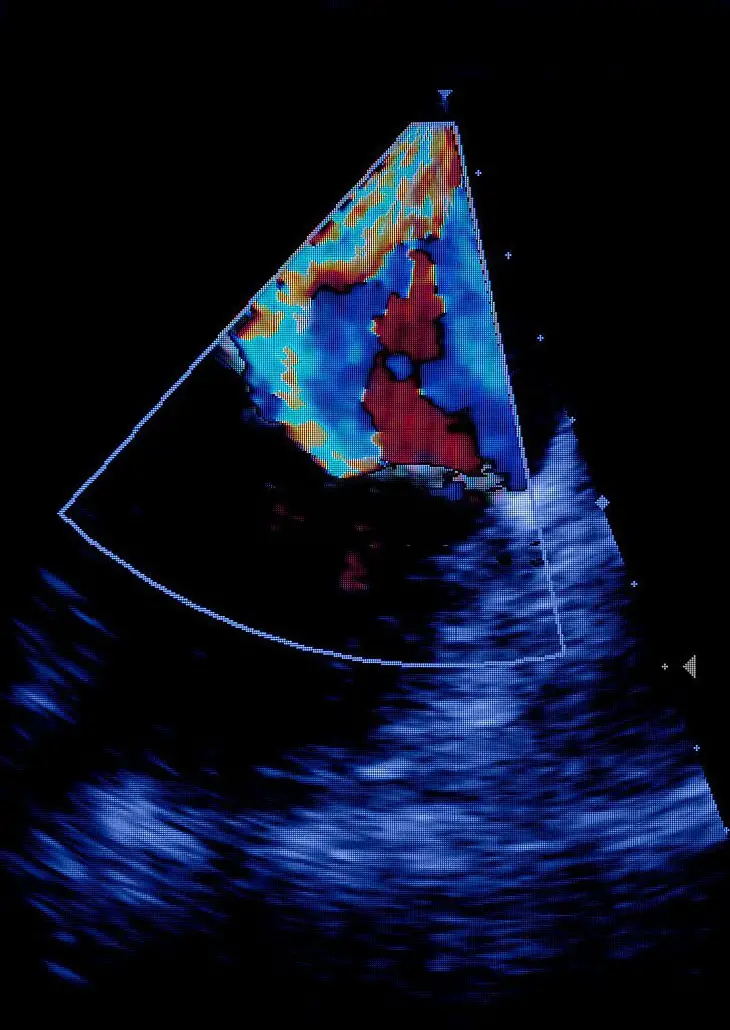

During the 20 week ultrasound anatomy scan, a trained technician or sonographer will use a handheld device (called a transducer) to send sound waves into your uterus. Most of the time, parents leave the 20-week scan with big smiles, having seen their baby in more detail than ever before

Source: ewherejfc.pages.dev Our terrifying 20 week anatomy scan , These sound waves bounce off the developing fetus and create images on a screen, which the technician can use to evaluate the baby's anatomy. There's a history of spina bifida in my family so I read up on everything the sonographer would check for and spoke to her before the scan so she would double check everything (spine, head circumference.

Source: rewrapfaz.pages.dev How To Deliver Bad News at Work NRMC Risk Resources , During the 20 week ultrasound anatomy scan, a trained technician or sonographer will use a handheld device (called a transducer) to send sound waves into your uterus. The 20-week scan includes a definite check of the child, checking for things like fetal peculiarities